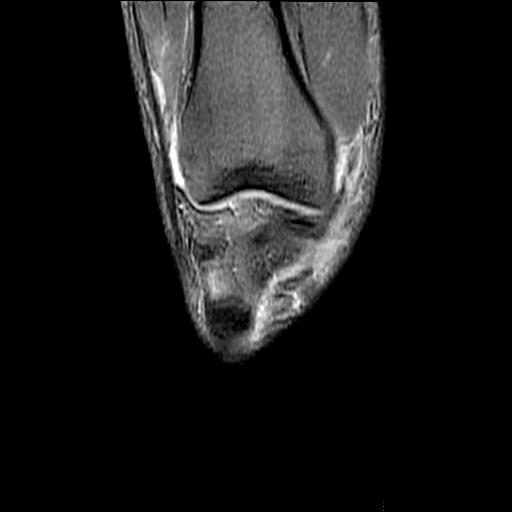

40岁男性,右膝关节外伤,x光平片示,髁间隆突撕脱骨折。

髁间隆突撕脱骨折;内侧副韧带损伤。

1、内侧副韧带撕裂;

2、前交叉韧带撕裂;

3、滑膜炎伴关节腔积液。

内侧副韧带撕裂及关节腔积液是肯定的,但是前交叉撕裂确定吗?会不会有容积效应的因素,因为前一张前交叉显示清楚,连续性良好,且较光滑。请问楼主有关节镜支持吗?我们医院也经常有这样的患者,但苦于没有关节镜,而无法对照、证实(除非完全断裂),出现了不同的诊断结果只能毫无意义的争论。

1、前交叉韧、内侧副韧带撕裂;

2、外侧半月板后角撕裂;

3、关节腔积液。4、髁间脊撕脱骨折。

除了关节积液外并无韧带撕裂,acl胫侧附着点有2束,正常情况下脂肪信号。此病例应加做压脂像以便观察是否有骨损伤。

、内侧副韧带撕裂;

2、前交叉韧带撕裂